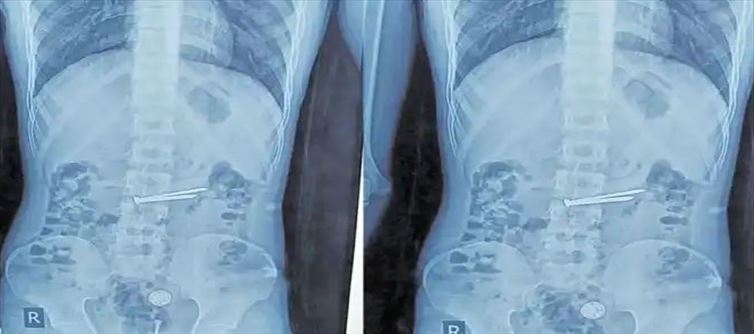

అయితే ఇటీవల అతను ఉన్నట్టుండి తీవ్రమైన కడుపునొప్పితో కేకలు వేయడం మొదలుపెట్టాడు. దీంతో పోలీసులు ఒక్కసారిగా అప్రమత్తమయ్యారు. ఇక జైల్లో ఉన్న ప్రాథమిక వైద్యులు చికిత్స చేసిన ఫలితం లేకపోవడంతో ఎస్కార్ట్ పోలీసులు సోహెల్ ని ఉస్మానియా ఆసుపత్రికి తరలించారు. అయితే పరీక్షలు చేసిన తర్వాత రిపోర్టులు చూసి డాక్టర్లు ఒక్కసారిగా కంగు తిన్నారు అని చెప్పాలి. ఎందుకంటే సోహెల్ ఎక్స్ రే పరిశీలించగా.. ఏకంగా కడుపులో షేవింగ్ బ్లేడ్లు, రెండు మేకులు, రెండు చిన్న రబ్బరు బంతులు, రెండు ప్లాస్టిక్ ప్యాకెట్లు ఇతర చిన్నపాటి వస్తువులు కూడా ఉన్నట్లు పోలీసులు గుర్తించారు.

అయితే ప్లాస్టిక్ ప్యాకెట్లలో గంజాయి ఉంది అని అనుమానంతో వాటిని డాక్టర్లు ల్యాబ్ కు పంపించారు అని చెప్పాలి. ఇక ఎండోస్కోపీ ద్వారా ఎంతో విజయవంతంగా ఆ ఖైదీ కడుపులో ఉన్న వస్తువులను కూడా బయటికి తీయగలిగారు వైద్యులు. ప్రస్తుతం అతని ఆరోగ్యం నిలకడగానే ఉందని వైద్యులు తెలిపారు. అయితే సదరు ఖైది ఎందుకు ఎప్పుడు ఆ వస్తువులను మింగాడు అన్న విషయాన్ని మాత్రం పోలీసులు అడిగిన వెల్లడించలేదు. ఈ క్రమంలోనే అతనికి మానసికపరమైన సమస్యలు ఏమైనా ఉన్నాయా అని ఇక వైద్యులు పరీక్షలు చేస్తూ ఉండడం గమనార్హం.